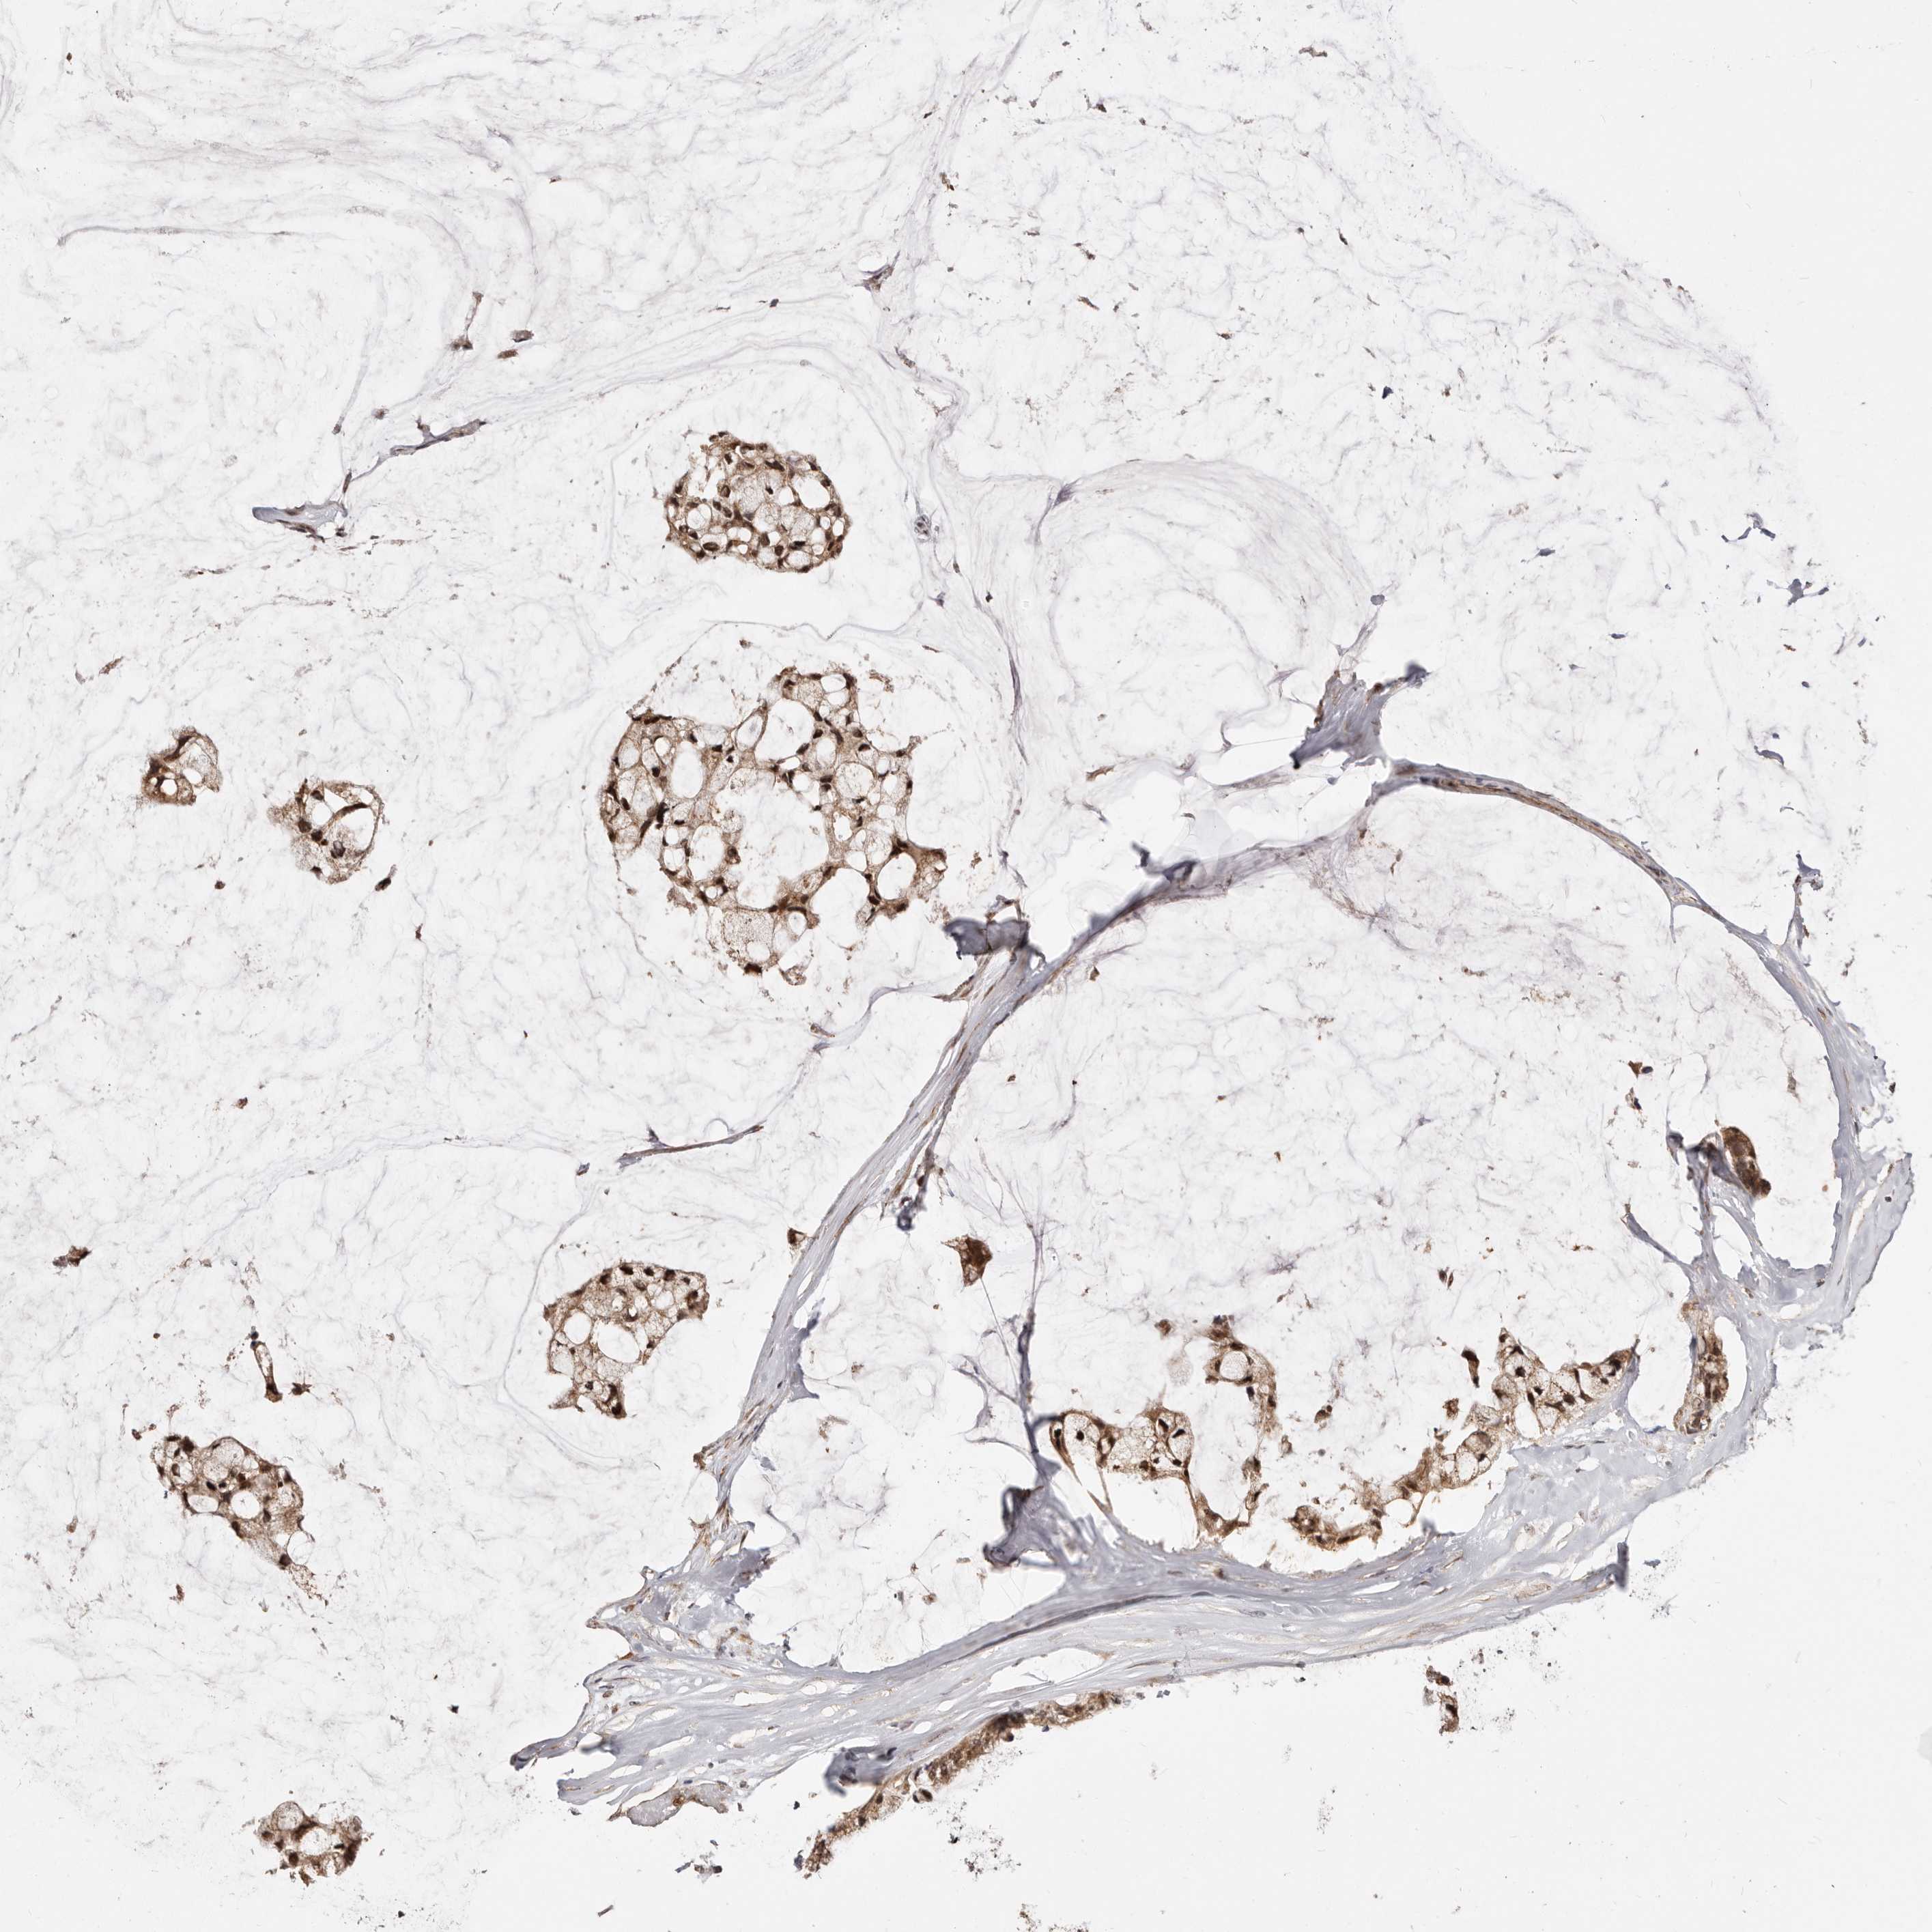

OVARIAN CANCER - Protein expressioni

A mouse-over function shows sample information and annotation data. Click on an image to view it in a full screen mode. Samples can be filtered based on level of antibody staining by selecting one or several of the following categories: high, medium, low and not detected. The assay and annotation is described here.

Note that samples used for immunohistochemistry by the Human Protein Atlas do not correspond to samples in the TCGA dataset.

Antibody stainingi

Antibody staining in the annotated cell types in the current human tissue is reported as not detected, low, medium, or high, based on conventional immunohistochemistry profiling in selected tissues. This score is based on the combination of the staining intensity and fraction of stained cells.

Each image is clickable and will lead to virtual microscopy that enables deeper exploration of all samples and also displays staining intensity scores, fraction scores and subcellular localization as well as patient and tissue information for each sample.

Antibody HPA028703

High

Medium

Low

Intensity

Moderate

Quantity

75%-25%

Location

Cytoplasmic/membranous,nuclear

None

Cystadenocarcinoma, mucinous, NOS

Cystadenocarcinoma, serous, NOS